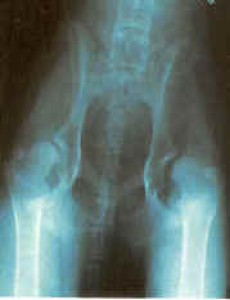

Snímky zdravých kloubů: